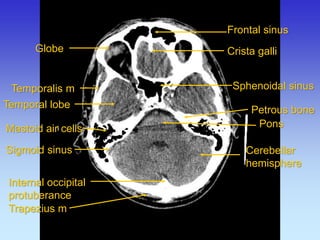

Crista galli

Internal occipital protuberance

Frontal sinus

Pons

Mastoid air cells

Petrous bone

Sphenoidal sinus

Temporalis m

Temporal lobe

Cerebellar hemisphere

Trapezius m

Sigmoid sinus

Globe